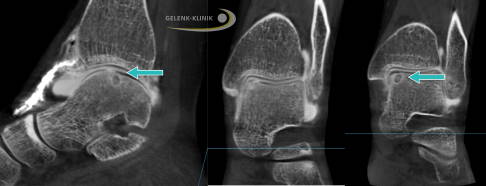

Dafür erfolgen zur Stellungskontrolle der einzelne Knochen des Sprunggelenks Röntgenaufnahmen unter Belastung. Gleichzeitig kann eine Knochenschichtung im Rahmen einer DVT (digitale Volumentomographie) erstellt werden. Auch die klinische Untersuchung zur Klärung der Bandstabilität des Sprunggelenkes ist unbedingt notwendig.

Die Kernspintomographie (MRT) ist wenig geeignet, um einen Knorpelschaden am Sprungbein direkt darzustellen. Dafür zeigt das MRT gegebenenfalls ein Knochenödem oder Knochenzysten als Zeichen der Knochenreaktion.

Arthrografie zur Diagnose eines Knochenschadens im Sprunggelenk

Stellt der Arzt eine Veränderung der Knochenstruktur fest, muss er immer entscheiden, ob diese Schädigung durch einen Knorpelschaden entstanden ist oder ob der Knochen ohne eine Schädigung des Knorpels erkrankt ist wie bei der Osteochondrosis dissecans.

Hier sind verschiedene Ansätze in der Diagnostik sinnvoll. Der direkte Nachweis einer Schädigung der abdichtenden und dämpfenden Knorpelschicht kann nur im Rahmen einer invasiven Arthrografie erfolgen.

Hierbei wird die Gelenkschmiere mit einem jodhaltigen Kontrastmittel versetzt. Um die Verteilung der Gelenkschmiere genau darzustellen, benötigt man eine Darstellung mit Röntgenstrahlen ähnlich einer Computertomographie oder einer digitalen Volumentomographie (DVT). Letztere kann unter Belastung durchgeführt werden, womit sich zeitgleich eine Stellungsbeurteilung durchführen lässt.